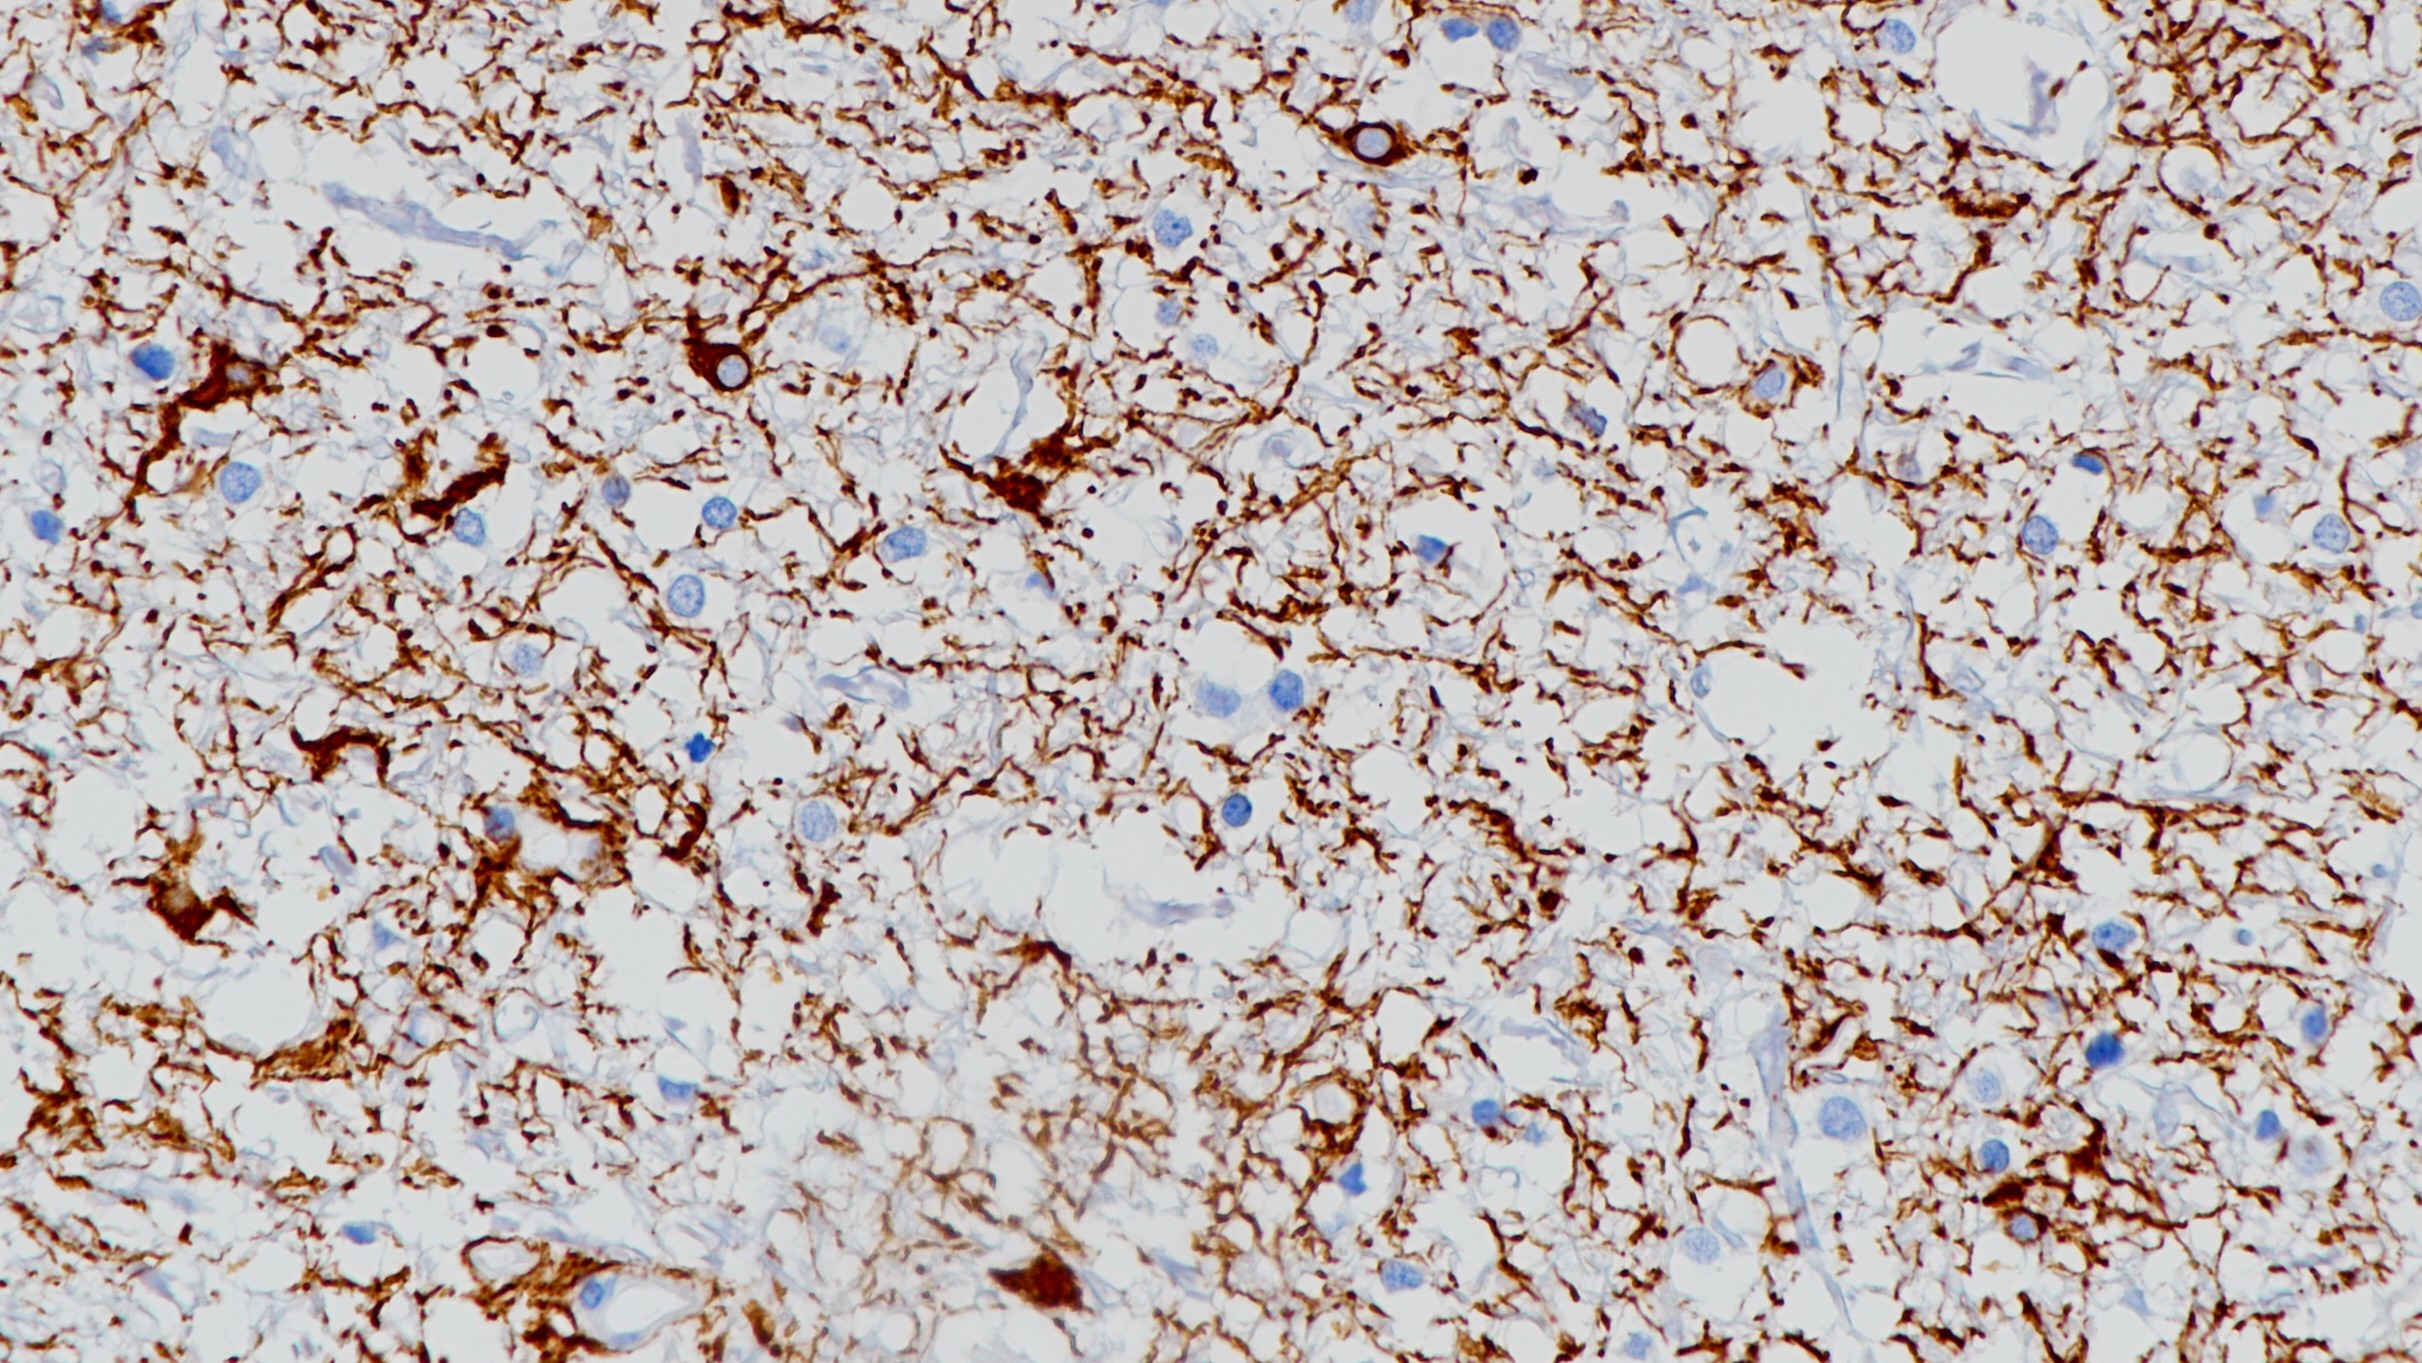

2.Xu QZ, Duan HL, Lu DH. Immunohistochemical quantitative study of glial fibrillary acid protein and vimentin astrocytomas. Chuang-hua Ping Li Hsueh Tsa Chih 1994 Apr;23(2):66-68.